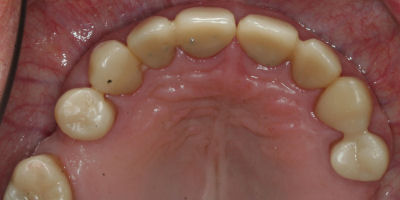

Opening Bite

Repair Worn Teeth